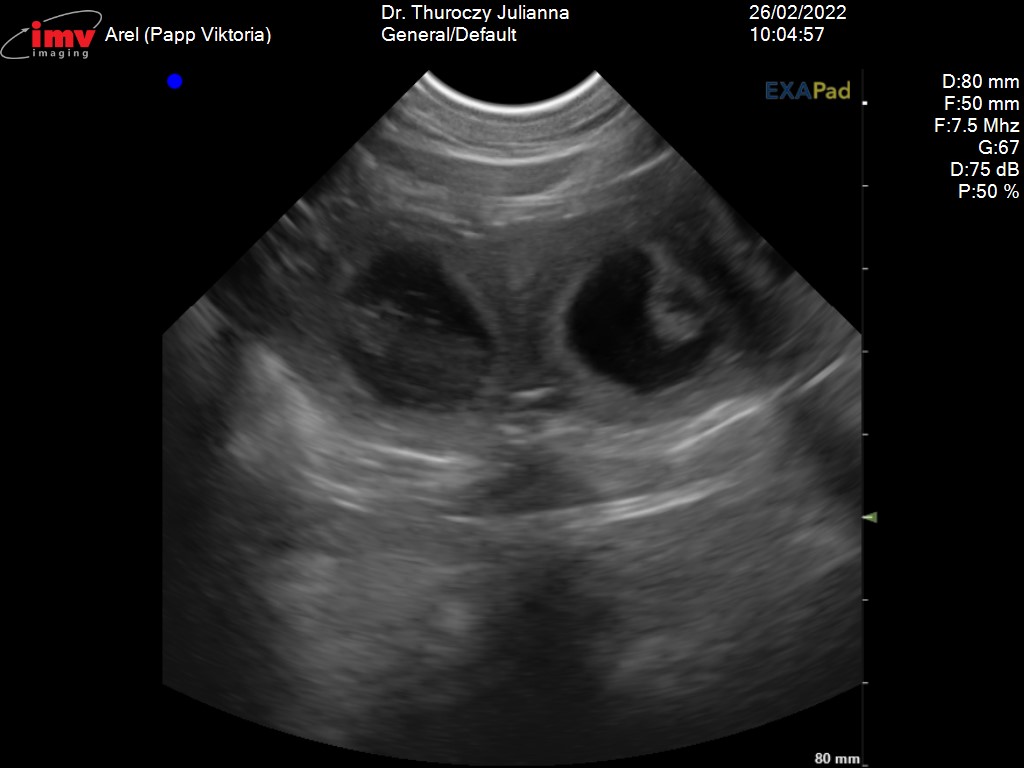

Az élet egyik nap elvesz a másik nap ad. A szombati ultrahang megerősítette hogy Arel és Beso pároztatása sikeres volt. Arel vemhes. Köszönjük Joanna a bizalmat. Gratulálunk Besónak, ügyes volt.